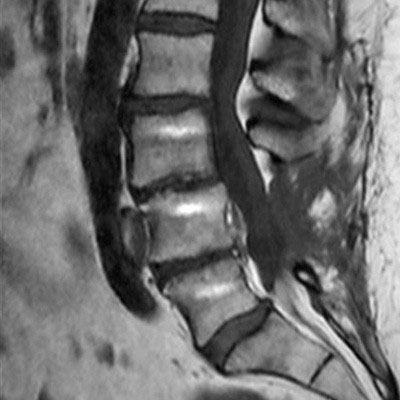

Lumbar Spine with metal implant, routine and fast

Utrecht Medical Center, The Netherlands

**Only for use with MR Safe or MR Conditional Implants by strictly following the Instructions for Use.